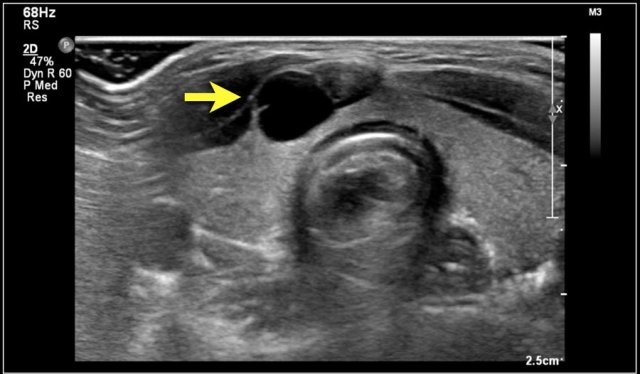

Here images of a six-month old boy with a vocal cord paralysis.

The MRI examination shows a mass between the parotid and submandibular gland (yellow arrow).

The signal characteristics are equal to the thymus (green arrow).

Ultrasound confirmed an ectopic thymic remnant (yellow arrow), with identical sonographic characteristics as the orthotopic thymus (green arrow).

Left: orthotopic thymus; right: ectopic thymus